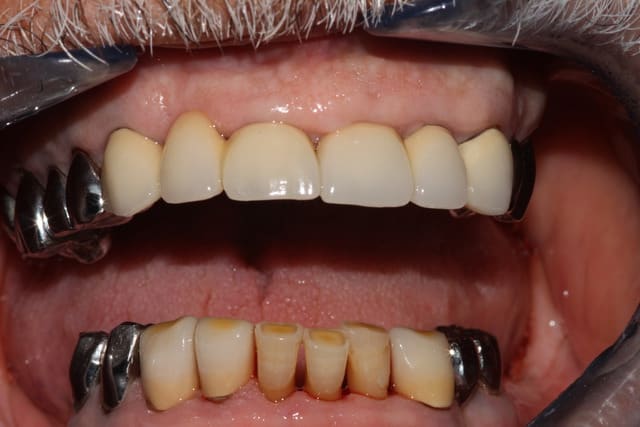

Ca c'est un boulot qui m'a fait extrêmement plaisir, parce que je trouve qu'on touche là à l'essence même de notre activité: permettre aux gens de manger.

Ce monsieur, 80 piges au compteur, est arrivé avec des vieilles provisoires, des gros compos, tout se cassait la figure... "Oh, mais à mon âge est-ce que ça vaut bien le coup de mettre des sous dans les dents..."

Pas de vraies difficultés techniques, pas de recherche esthétique marquée, du métal, on a reconstruit une occlusion de 5 à 5 seulement. Mais niveau qualité de vie, j'aimerai être toujours aussi efficace.

Photos un an après la pose. Pano avant.